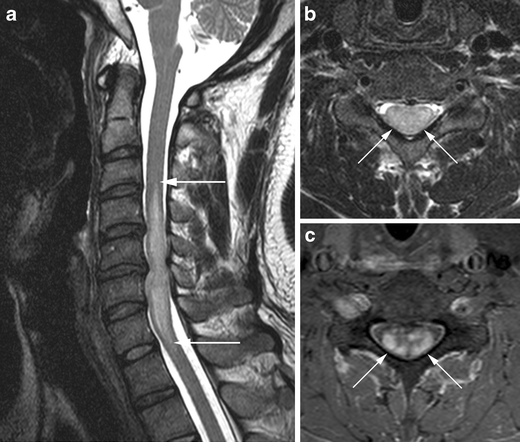

Compressive Myelopathy

Compressive myelopathy is a medical condition characterized by the compression of the spinal cord, resulting in neurological deficits.